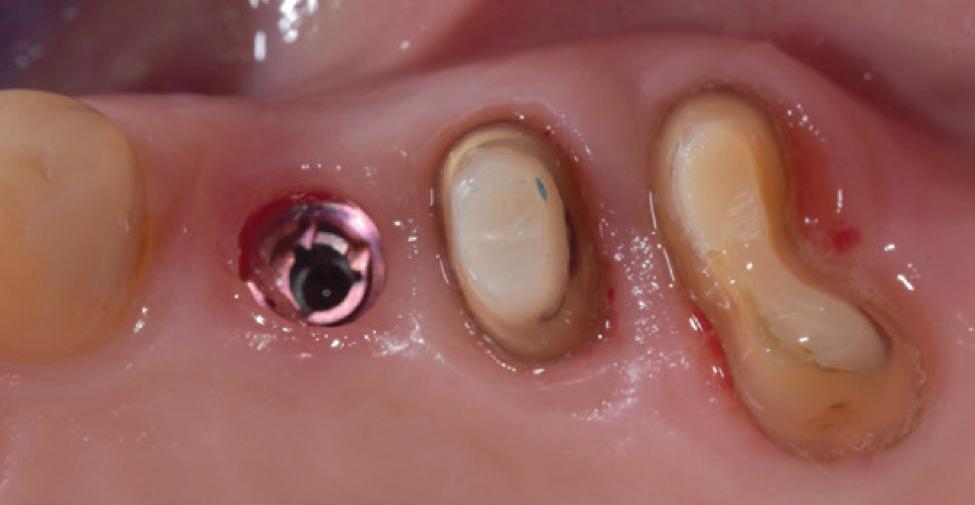

Typically, Grin Doctors provide patients undergoing orthodontic treatment, whether with brackets and wire or aligners, with a Grin Scope that attaches to their smartphone. The innovative Grin app then guides patients to video scan their teeth in treatment in front of a mirror. These scans are then immediately available to the clinician for review via the doctor portal to monitor treatment progress and address any clinical issues.

Importantly, at the heart of it all is the Grin Care Specialist—an extension of your team who ensures virtual care is seamless, your workflows stay efficient and your patients remain connected, engaged and on track every step of the way. Human Grin Care Specialists are able to maintain a dialogue with patients and alert Grin Doctors when required, increasing efficiency.